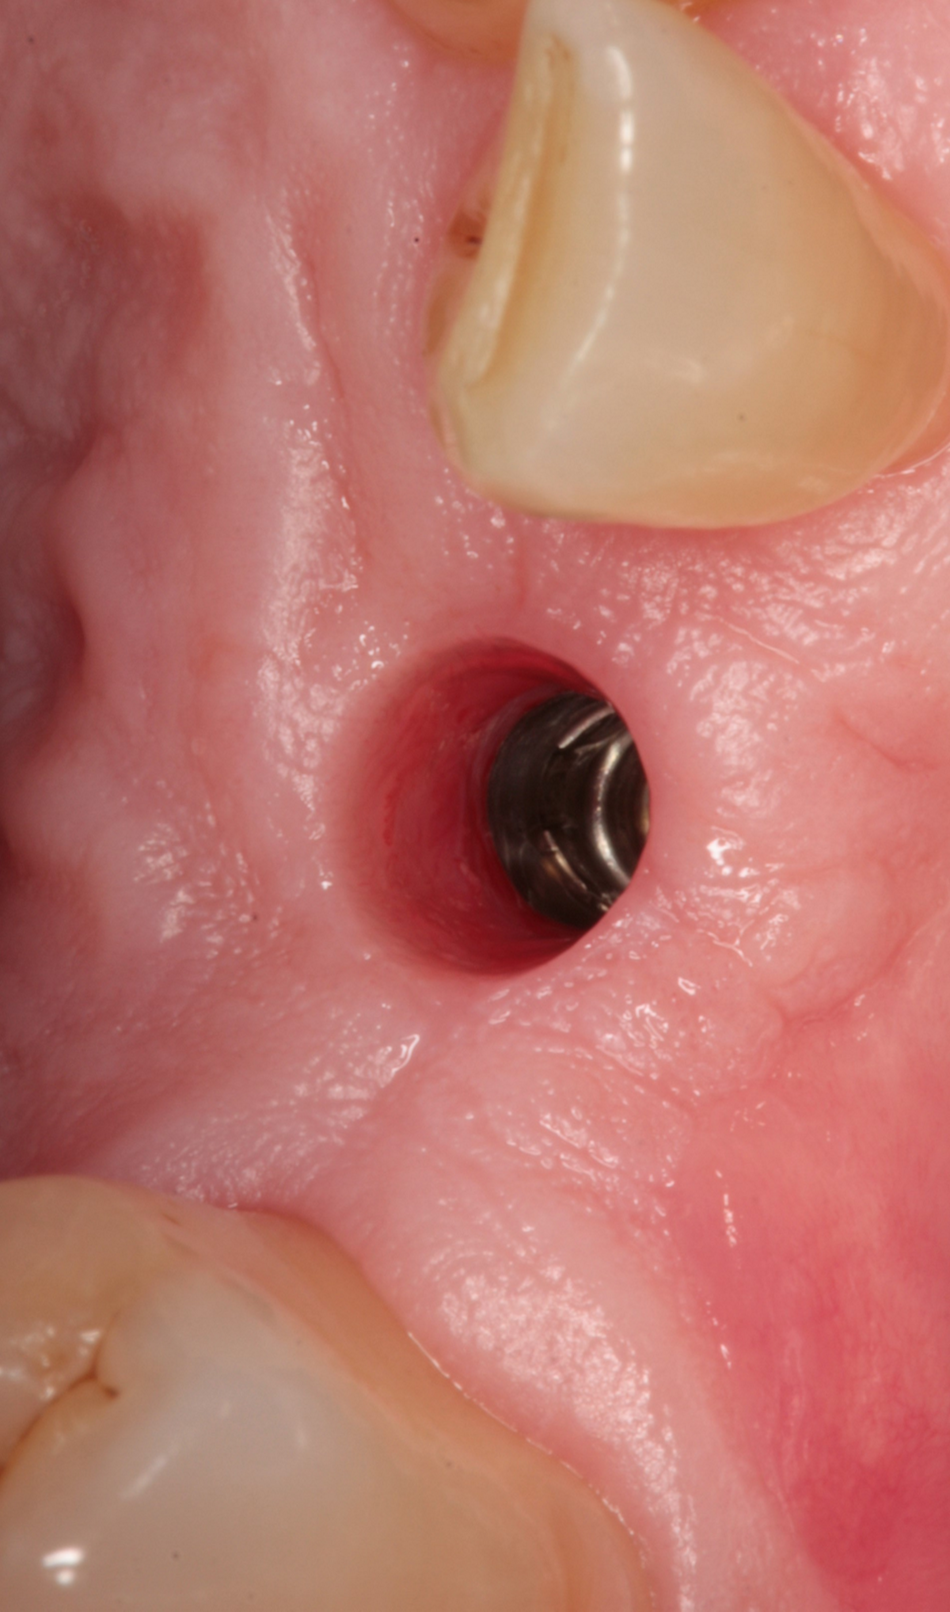

At the time of the second stage (Figs. 8- 10), we screwed a classic titanium healing abutment into implant 13 and a ceramic healing abutment on implant 23 (Figs. 11-14). The Ceramic Healing Abutments are composed of an external Zirconia body, while the internal part consists of a titanium screw that allows the tighten into the implant. We therefore made sure to put a chlorhexidine gel on the titanium part to avoid bacterial contamination.

Following 3 months, digital impressions were taken. The permanence of a satisfying amount of keratinized tissue around the implants was obtained thanks to the conservative surgical intervention, preserving the necessary portion of keratinized mucosa aimed to obtain good soft tissue conditions (Figs 15-18).